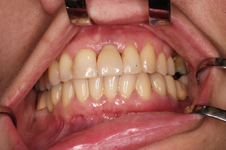

V případě chybění většího počtu zubů v postranních úsecích čelistí je možné ošetření pomocí implantátů, které nahradí ošetření pomocí snímacích náhrad kotvených na zbývajících zubech nebo patře.

Podmínkou je opět dostatečné množství kosti.

Protetické řešení může být pomocí můstku, který je kotvený na implantátech nebo pomocí jednotlivých korunek na implantátech.